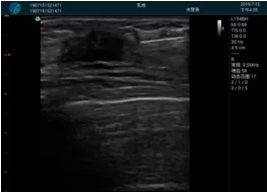

病例二:

腺體內(nèi)部清晰顯示一低回聲塊影,形態(tài)不規(guī)則,邊界模糊,邊緣呈毛刺狀,內(nèi)部見砂礫樣鈣化

M20引導(dǎo)下穿刺活檢術(shù)

M20引導(dǎo)下平面內(nèi)穿刺取出的腫塊組織